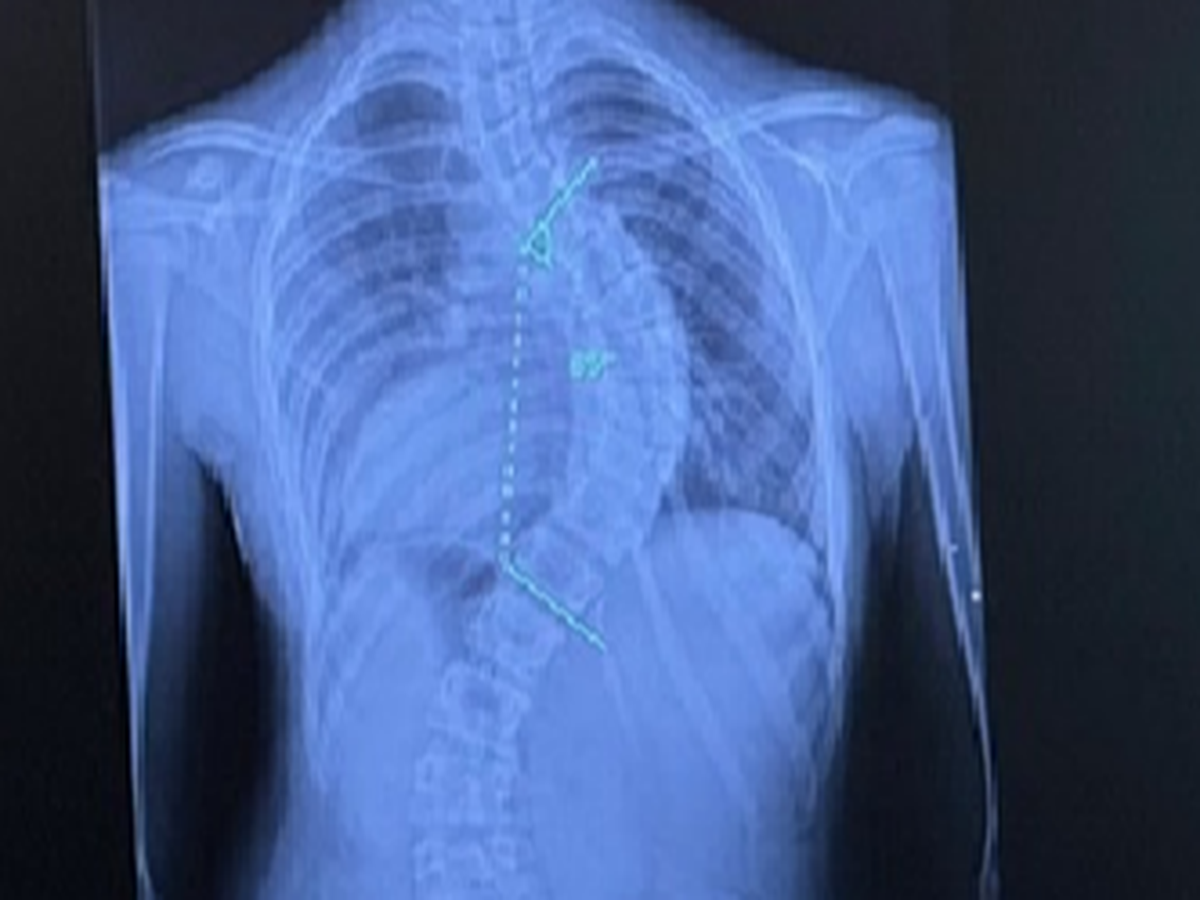

Hello! I am Rebeckah Finchum, and I am trying to help raise money for my granddaughter to have scoliosis surgery with rods in her back. Her mother has to pay the majority of the money upfront to cover the deductible on her insurance policy. She will also have to be in the hospital post-surgery for about a month to recover and do physical therapy to help heal and strengthen her back.